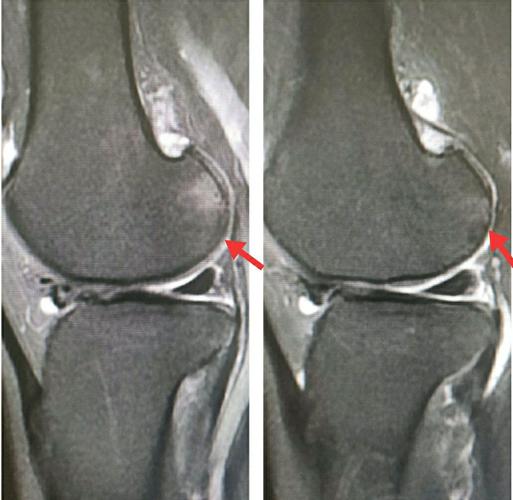

膝关节核磁共振读片

膝关节的核磁片子,半月板有损伤,自己也看不太懂,帮我

【关节影像】膝关节的磁共振(mri)解剖表现